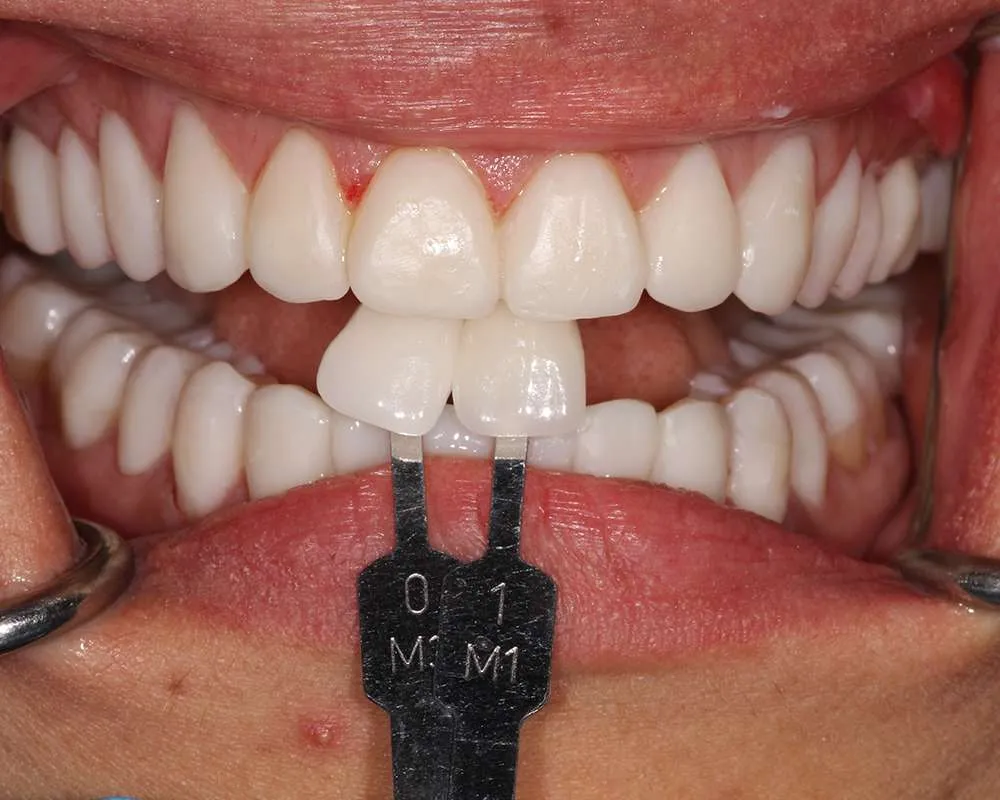

The process of getting ultra-thin veneers typically involves several steps. First, during the initial consultation, we will discuss your goals and take impressions and photographs of your teeth. Next, we will minimally prepare your teeth generally less than 0.5mm of preparation (sometimes little or no preparation is needed depending on the design). Then you'll leave with a 'trial smile' and temporary veneers in place, after which we'll have a follow-up appointment the next day for final evaluation of your temporary veneers for tweaks and fitting to help guide the lab to your custom smile. Your veneers are finally crafted in a premier dental lab. Finally you'll return to the office where your custom, ultra-thin veneers are bonded to your teeth using biocompatible materials. The entire process usually takes one to four weeks from start to finish depending on the lab and complexity of the case.

Ultra-thin veneers are crafted from high-quality materials that closely resemble the look and feel of natural teeth. The translucency and texture of these veneers mimic the appearance of real enamel, ensuring that your smile looks natural and aesthetically pleasing. Each veneer is custom-made to match the color, shape, and size of your existing teeth, blending seamlessly with your natural smile. This attention to detail ensures that your veneers are virtually indistinguishable from your natural teeth, providing you with a flawless, beautiful smile.